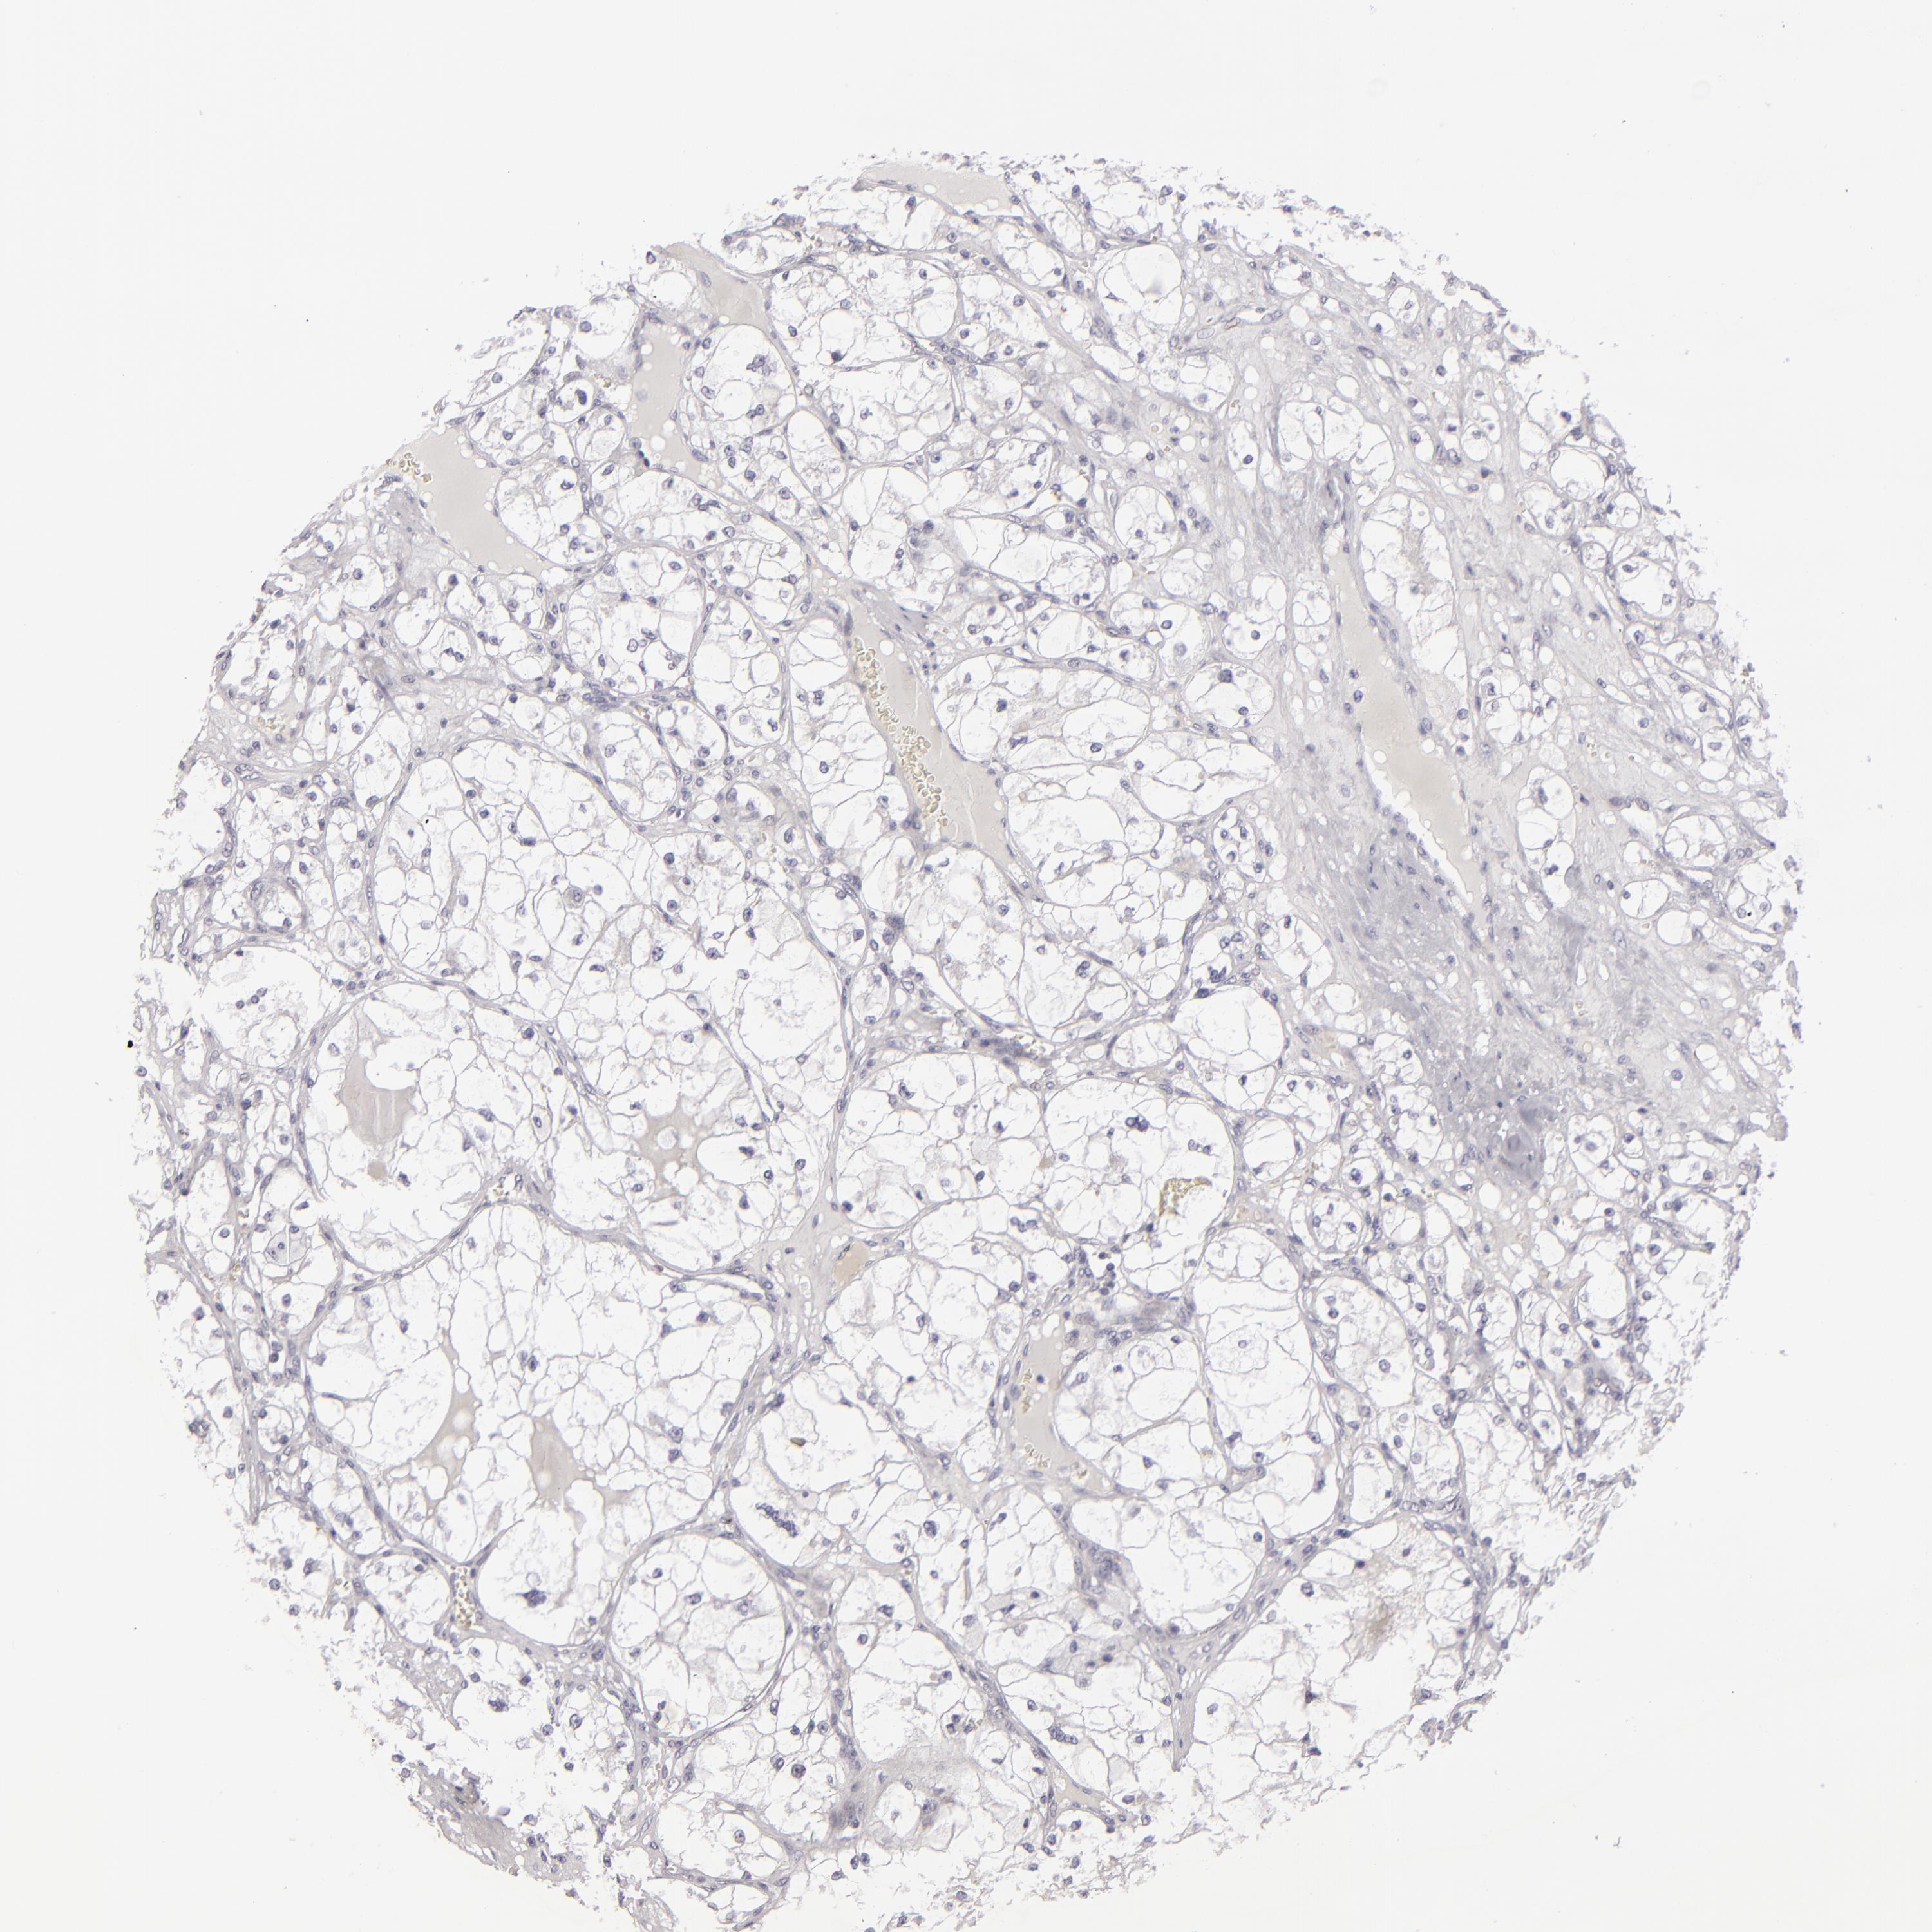

KIDNEY RENAL CLEAR CELL CARCINOMA (TCGA) - Interactive survival scatter ploti

The Survival Scatter plot shows the clinical status (i.e. dead or alive) for all individuals in the patient cohort, based on the same data that underlies the corresponding Kaplan-Meier plots. Patients that are alive at last time for follow-up are shown in blue and patients who have died during the study are shown in red.

The x-axis shows the expression levels (FPKM) of the investigated gene in the tumor tissue at the time of diagnosis. The y-axis shows the follow-up time after diagnosis (years). Both axes are complimented with kernel density curves demonstrating the data density over the axes. The top density plot shows the expression levels (FPKM) distribution among dead (red) and alive patients (blue). The right density plot shows the data density of the survived years of dead patients with high and low expression levels respectively, stratified using the cutoff indicated by the vertical dashed line through the Survival Scatter plot. This cutoff is automatically defined based on the FPKM cutoff that minimizes the p-score. The cutoff can be changed by dragging the vertical line or by entering a cutoff value in the square labeled "Current cut-off".

Under the Survival Scatter plot the p-score landscape (black curve; left axis) is shown together with dead median separation (red curve; right axis). Dead median separation is the difference in median mRNA expression between patients who have died with high and low expression, respectively. It is calculated as follows: median FPKM expression of dead patients with high expression - median FPKM expression of dead patients with low expression. This is intended to aid the user in visually exploring custom cutoffs and the associated p-scores and dead median separation.

Individual patient data is displayed and can be filtered by clicking on one or more of the category buttons on the top of the page. Categories describing expression level and patient information include: high, low, alive, dead, female, male and tumor stages. The scale of the x-axis can be toggled between linear and log-scale by clicking on the "x log" button. Mouse-over function shows TCGA ID, patient information and mRNA expression (FPKM) for each patient.

& Survival analysisi

Kaplan-Meier plots summarize results from analysis of correlation between mRNA expression level and patient survival. Patients were divided based on level of expression into one of the two groups "low" (under cut off) or "high" (over cut off). X-axis shows time for survival (years) and y-axis shows the probability of survival, where 1.0 corresponds to 100 percent.

JUP is validated prognostic, high expression is favorable in Kidney Renal Clear Cell Carcinoma (TCGA)

Best expression cut offi

Based on the FPKM value of each gene, patients were classified into two groups and association between prognosis (survival) and gene expression (FPKM) was examined. The best expression cut-off refers the FPKM value that yields maximal difference with regard to survival between the two groups at the lowest log-rank P-value. Best expression cut-off was selected based on survival analysis .

When clicking on this number, the vertical dashed line indicating cut-off, the interactive survival plot, and the Kaplan-Meier curve will be adjusted to show results based on the best expression cut-off.

: 57.58

TCGA RNA samplesi

RNA-seq data is reported as average FPKM (number Fragments Per Kilobase of exon per Million reads), generated by the The Cancer Genome Atlas (TCGA) .

Normal distribution across the dataset is visualized with box plots, shown as median and 25th and 75th percentiles. Points are displayed as outliers if they are above or below 1.5 times the interquartile range. FPKM values of the individual samples are presented next to the box plot.

Average pTPM 101.4

Number of samples 521